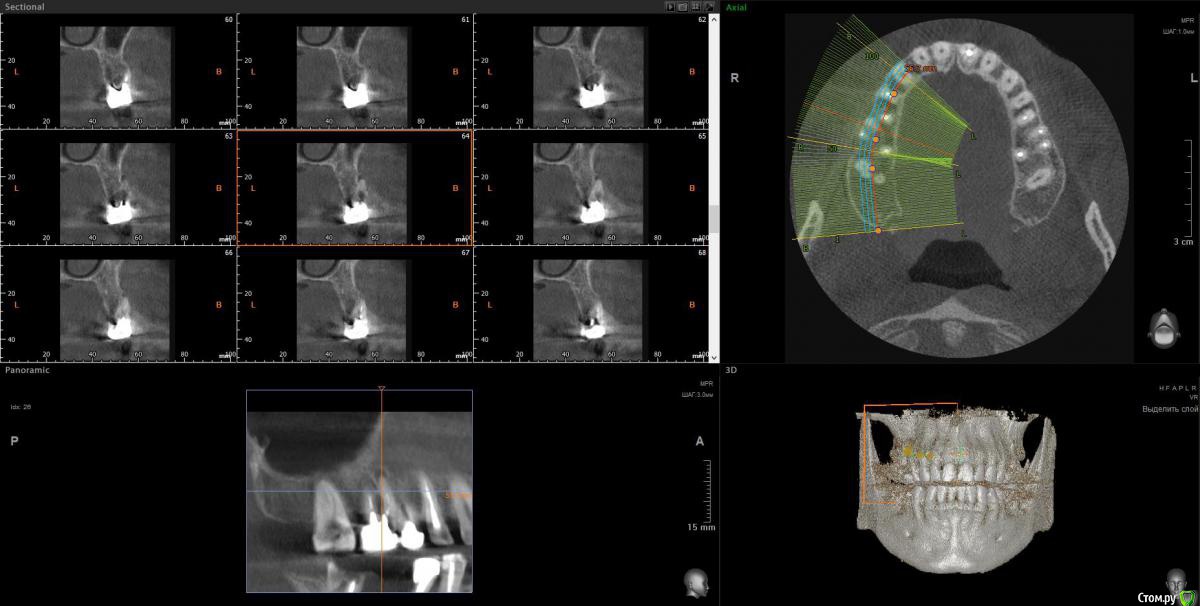

wladdX Опубликовано 12 февраля, 2018 Поделиться Опубликовано 12 февраля, 2018 Скрины 1 Ссылка на комментарий

Taurus007 Опубликовано 13 февраля, 2018 Автор Поделиться Опубликовано 13 февраля, 2018 wladdXОгромное спасибо за скриншоты. Я бы даже близко так не смог) Пришел расчет и анализ ТРГ. Заключение.pdf Ссылка на комментарий

Bier Опубликовано 22 февраля, 2018 Поделиться Опубликовано 22 февраля, 2018 Справа синуслифтинг не потребуется 100%Слева - возможно в области 26 зуба. Для оценки прикуса одного ТРГ мало, надо еще фото моделей. Вам их наверное делали? Ссылка на комментарий

Taurus007 Опубликовано 24 февраля, 2018 Автор Поделиться Опубликовано 24 февраля, 2018 Справа синуслифтинг не потребуется 100% Слева - возможно в области 26 зуба. А в целом, можно ли сейчас не трогать область, где возможно потребуется синуслифтинг, поскольку в практическом смысле это наименее проблемная область, хоть коронки и стоят уже 9 лет ? надо еще фото моделей. Вам их наверное делали? Не делали. Это как-то в домашних условиях возможно? Ссылка на комментарий